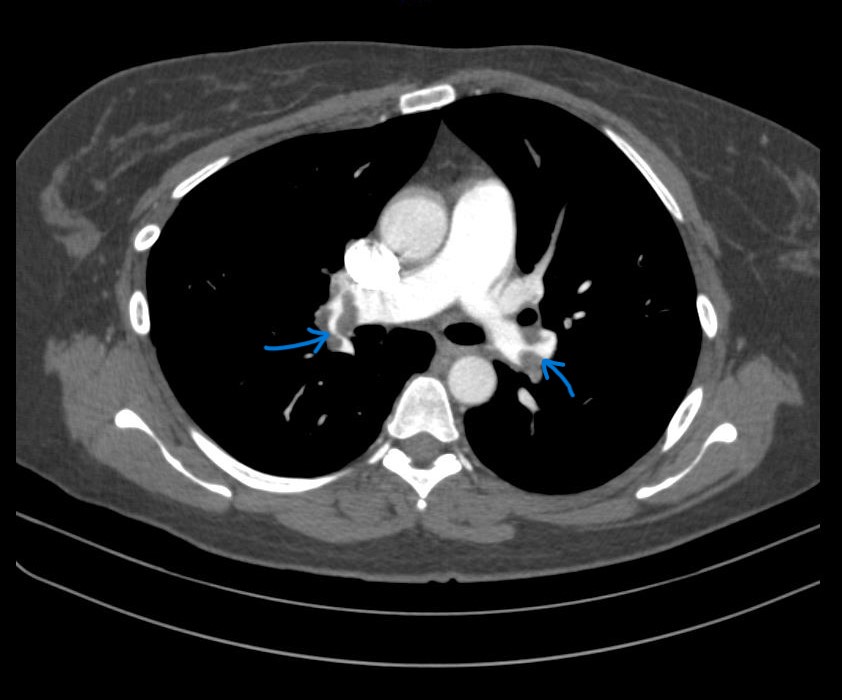

Her troponin T and D-dimer levels were both significantly elevated, at 289 pg/mL (normal < 14) and 3195 ng/mL, respectively. An ECHO revealed signs of right ventricular (RV) overload and dysfunction. Given the high clinical suspicion for pulmonary embolism, she was sent for a CT pulmonary angiogram, which confirmed a massive bilateral pulmonary embolism (PE). She was classified as Class V on the Pulmonary Embolism Severity Index (PESI) and diagnosed with intermediate-high risk PE.

Right femoral vein access was obtained under ultrasound and fluoroscopy guidance. A 6Fr multipurpose (MP) catheter was used to deliver a J-tip guidewire into the main pulmonary artery, which was then exchanged for a pigtail catheter. Digital subtraction angiography revealed filling defects in the truncus anterior and bilateral interlobar arteries. The 6Fr femoral sheath was upsized to a 16Fr sheath. The Penumbra ENGINE and Lightning Flash 2.0 system, with a 16Fr aspiration catheter, was primed. Using the MP catheter, the J-tip guidewire was delivered into the left pulmonary artery and exchanged for the 16Fr aspiration catheter. Multiple aspiration runs were performed using the computer-assisted vacuum thrombectomy system. The same steps were repeated for the right pulmonary artery. The procedure lasted 2 hours, with 1.2L of blood loss and approximately 6-8 cubic centimeters of fresh clots aspirated. The patient received 2 units of packed red blood cells during the procedure. Femoral access was closed with a figure-of-8 suture.